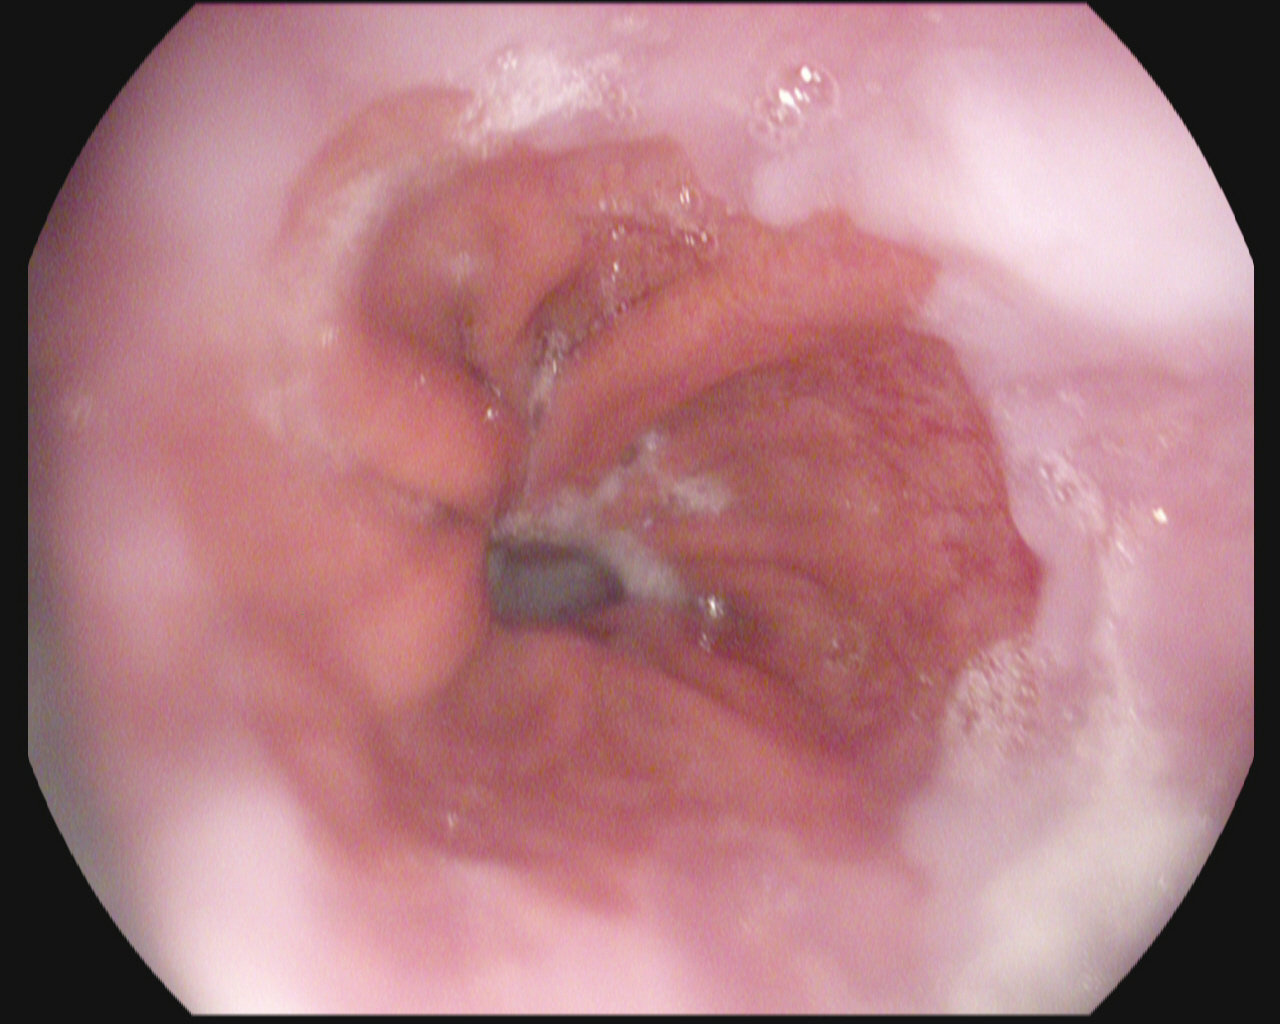

Image of a polyp from a colonoscopy

Polyps